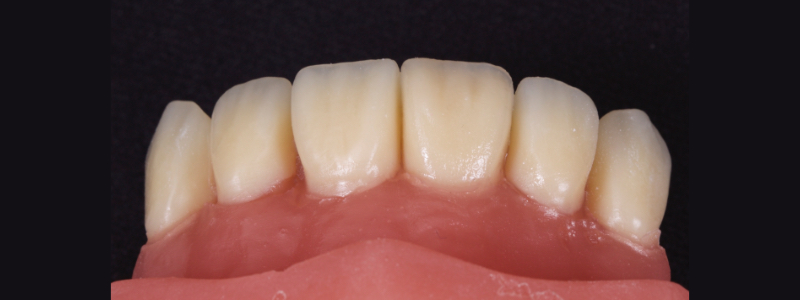

After deprogramming with a splint and occlusal equilibration, the anterior teeth were restored with direct composite resin using a minimal prep approach (Figs. 4 and 5). The occlusal scheme was idealized (Fig. 6).

In this case, a 23-year-old male presented with Ellis Class II fractures of both central incisors (Fig. 23). He had no interest in closing his diastema or restoring the peg laterals. A treatment plan was agreed upon to restore both central incisors with direct resin.